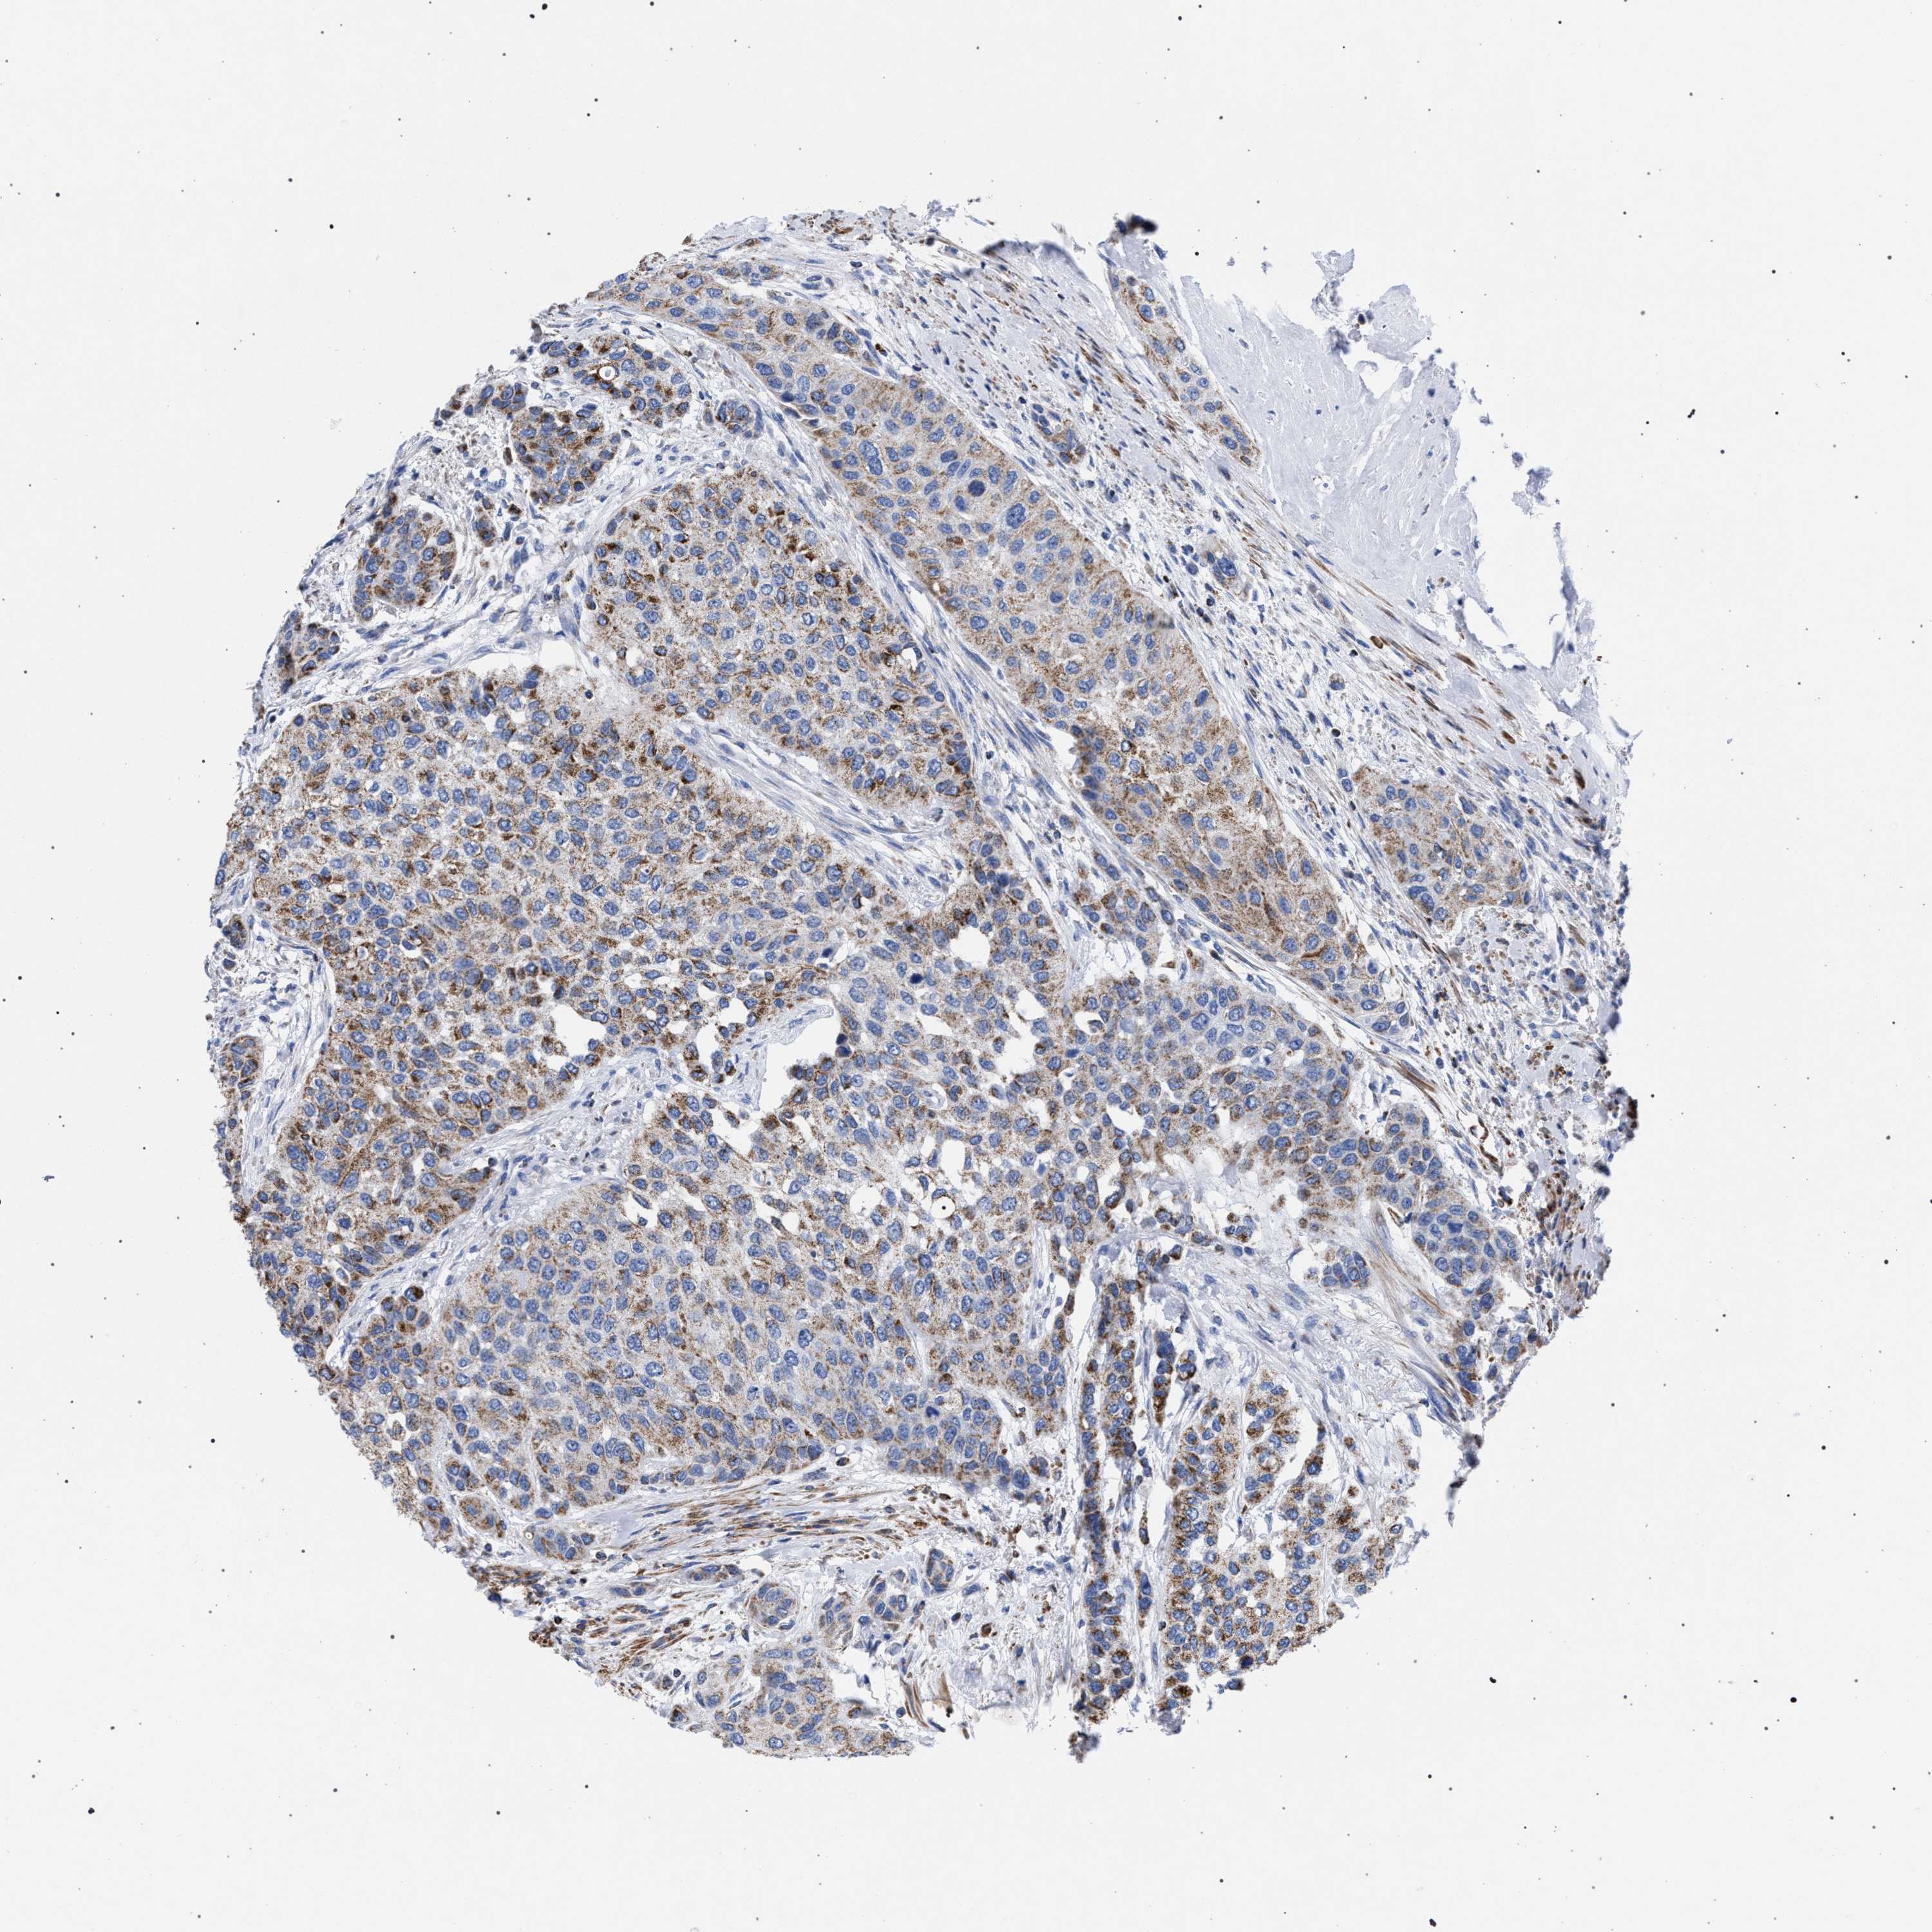

UROTHELIAL CANCER - Protein expressioni

A mouse-over function shows sample information and annotation data. Click on an image to view it in a full screen mode. Samples can be filtered based on level of antibody staining by selecting one or several of the following categories: high, medium, low and not detected. The assay and annotation is described here.

Antibody stainingi

Antibody staining in the annotated cell types in the current human tissue is reported as not detected, low, medium, or high, based on conventional immunohistochemistry profiling in selected tissues. This score is based on the combination of the staining intensity and fraction of stained cells.

Each image is clickable and will lead to virtual microscopy that enables deeper exploration of all samples and also displays staining intensity scores, fraction scores and subcellular localization as well as patient and tissue information for each sample.

Antibody HPA022271

Antibody CAB019284

Staining

High

Medium

Low

Not detected

Intensity

Strong

Moderate

Weak

Negative

Quantity

>75%

75%-25%

<25%

None

Location

Nuclear

Cytoplasmic/membranous

Cytoplasmic/membranous,nuclear

Urothelial carcinoma, Low grade

Urothelial carcinoma, High grade